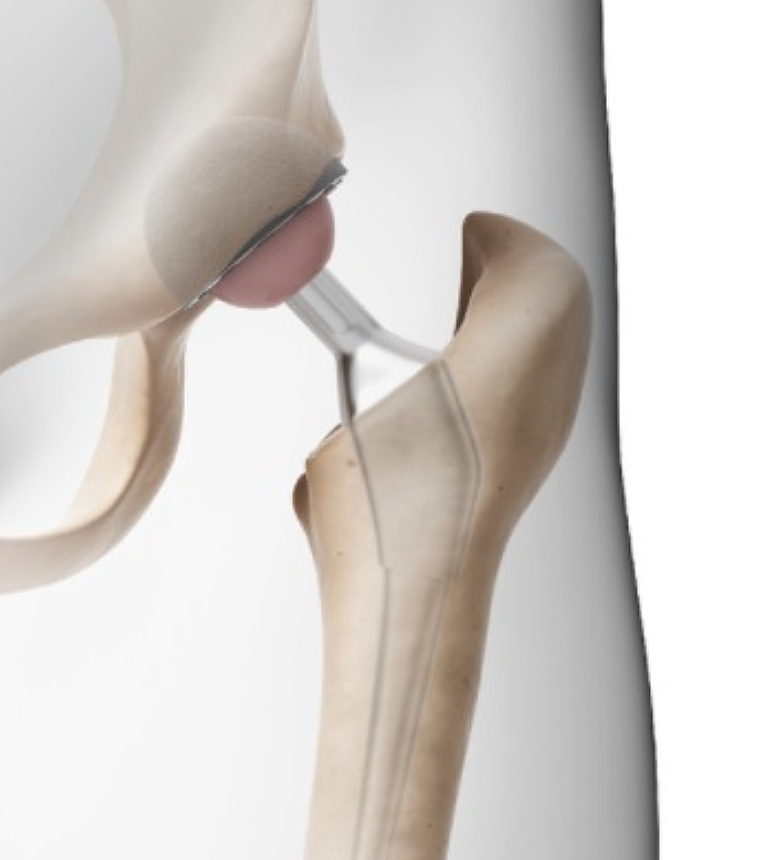

고관절은 골반 뼈 속에 공처럼 생긴 대퇴골의 골두가 맞물린 관절입니다. 대퇴골두는 다른 부위에 비해 혈액 순환 장애가 쉽게 올 수 있으며, 혈액 순환 장애는 대퇴골두 무혈성 괴사를 유발합니다. 뼈가 썩으면 몸의 하중을 정상적으로 견디지 못해 미세구조에 골절이 생기고, 심각한 통증이 발생합니다.

고관절 통증 증상은 조기에 발견하고 치료받는 것이 무엇보다 중요합니다. 고관절 손상이 심하지 않고 통증이 가볍다면 약물치료와 운동치료 등 보존적 치료를 통해 회복할 수 있습니다. 하지만 고관절 손상이 심하고 일상생활에 지장을 줄 만큼의 심한 고관절 통증 증상이 있는 경우라면 괴사된 관절을 제거하고 인공관절을 삽입하는 고관절의 인공관절 치환술을 해야 합니다.